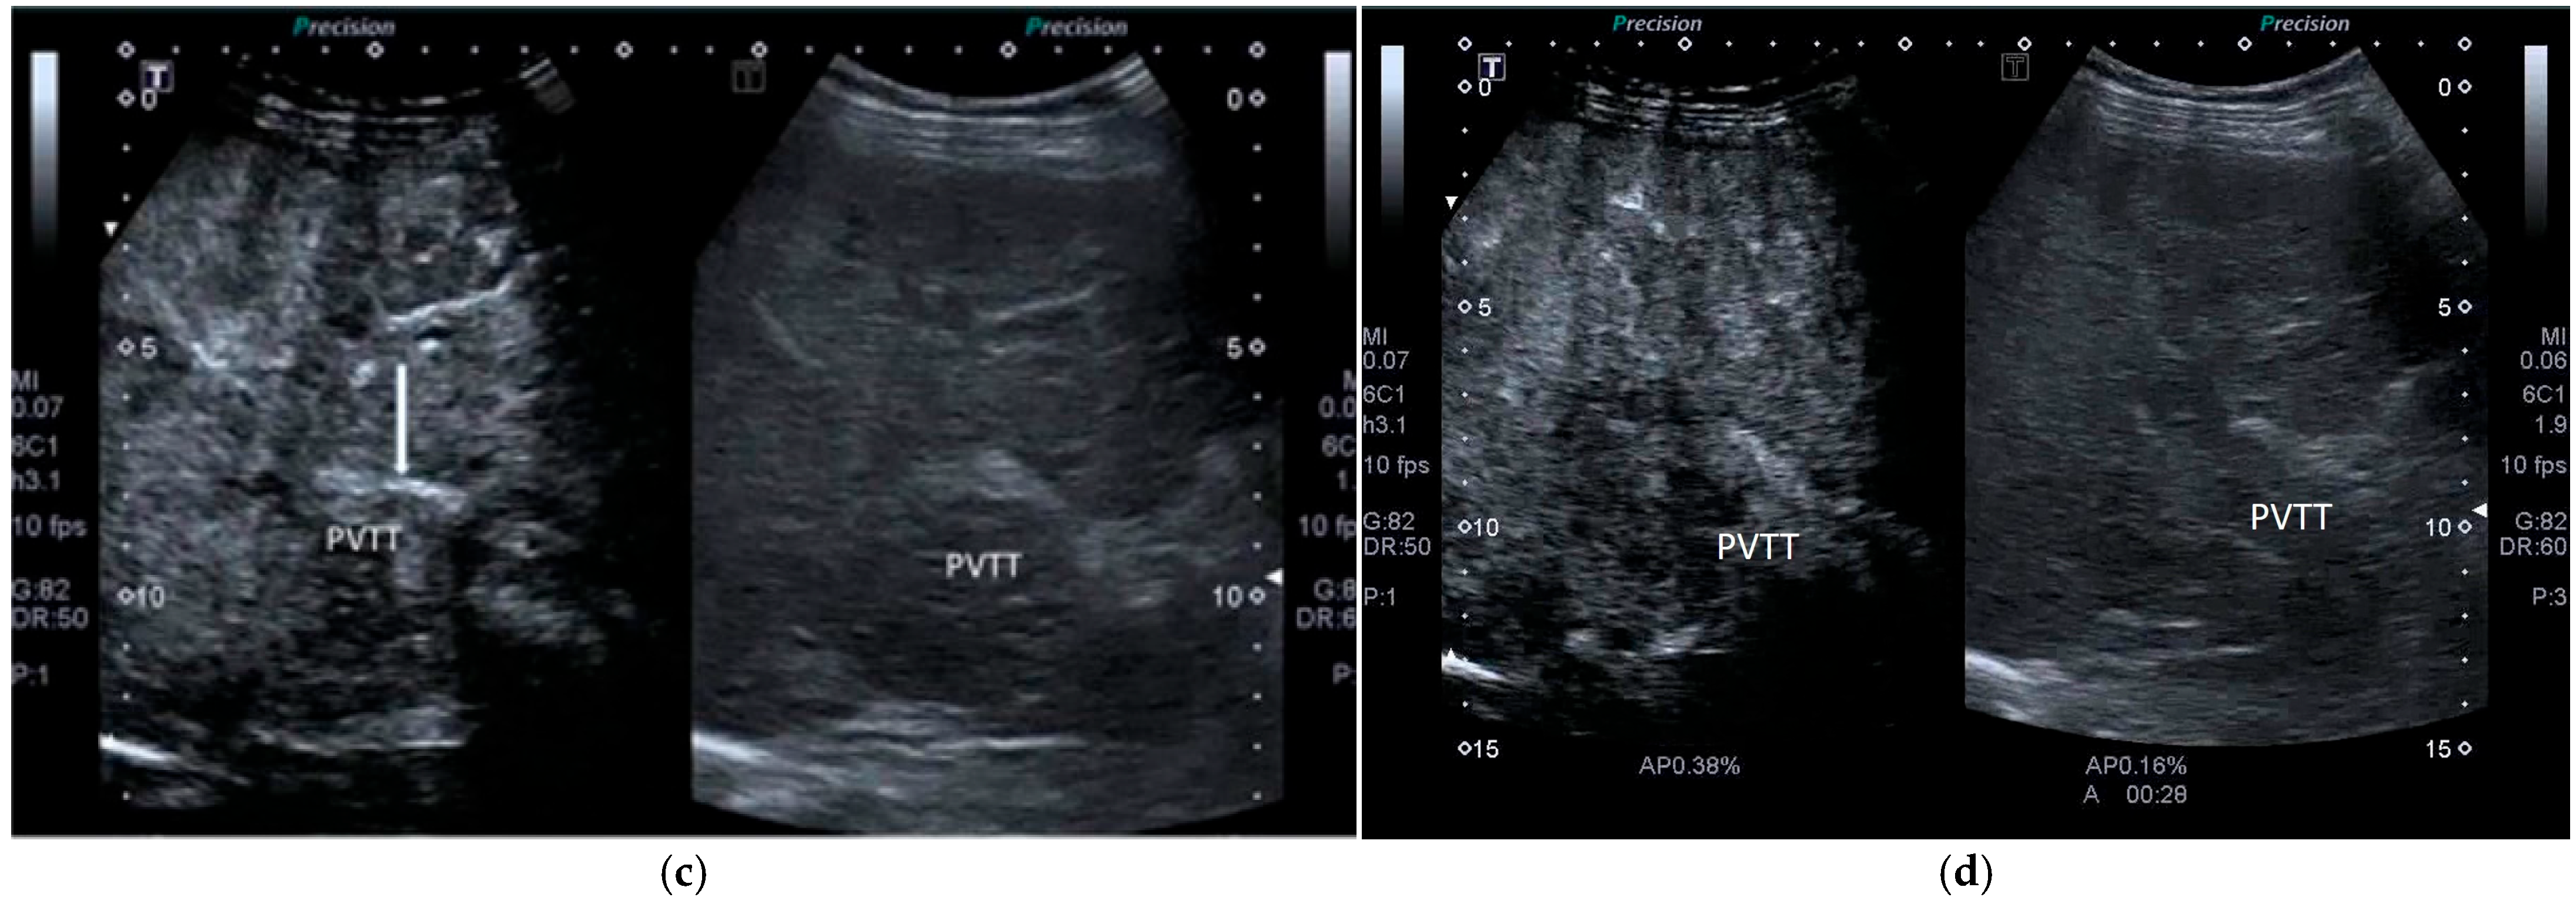

| POST-VIRAL HCC | MASLD HCC |

|---|---|

|

| |

| These characteristics would be focused more on the lack of malignancy rather than HCC. | |